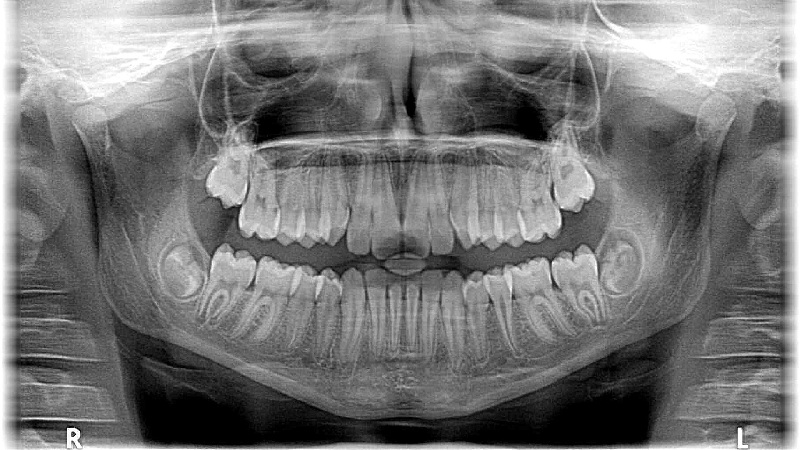

Tumore der Mundschleimhaut:

Der häufigste Tumor der Mundhöhle ist das Plattenepithelkarzinom (PEC), das bis zu 90 % der Tumore in diesem Bereich ausmacht. Die häufigsten Lokalisationen sind die Mundhöhle und die Zunge.

Risikofaktoren für das PEC sind neben Nikotin und Alkohol auch schlechte Mundhygiene sowie Viren. Nikotin und Alkohol erhöhen in Kombination signifikant das Risiko für die Entstehung eines PEC. Besonders der Mundboden ist aufgrund der Schwerkraft eine bevorzugte Lokalisation für Tumore, da sich schädliche Substanzen hier sammeln.